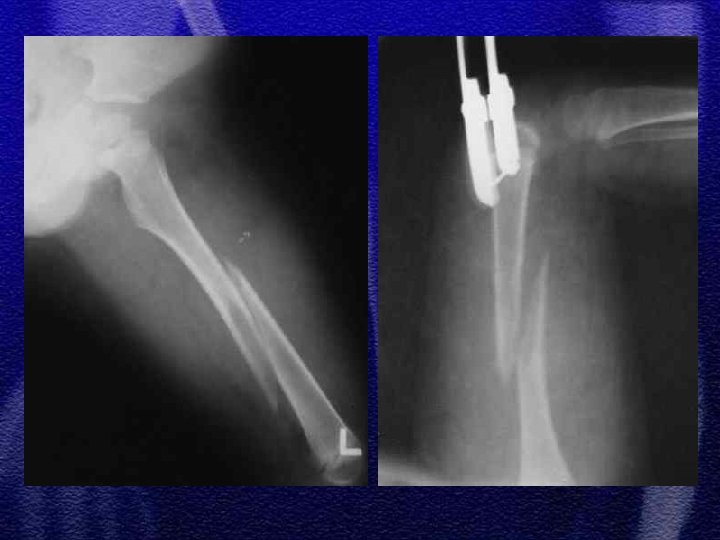

1. Występuje bardzo rzadko 2. Odcinek bliższy kości udowej u dzieci ma mały potencjał przebudowy, złamanie tej okolicy wymaga więc anatomicznego nastawienia i stabilnego zespolenia 3. Leczenie - złamania bez przemieszczenia -zachowawcze, z przemieszczeniem - wiązka drutów Kirschnera, śruby, płyta kątowa w złamaniach okolicy międzykrętarzowej

§ Jałowa martwica głowy kości udowej § Przedwczesne zarośnięcie chrząstki wzrostowej § Biodro szpotawe § Staw rzekomy (wyjątkowa rzadkość)